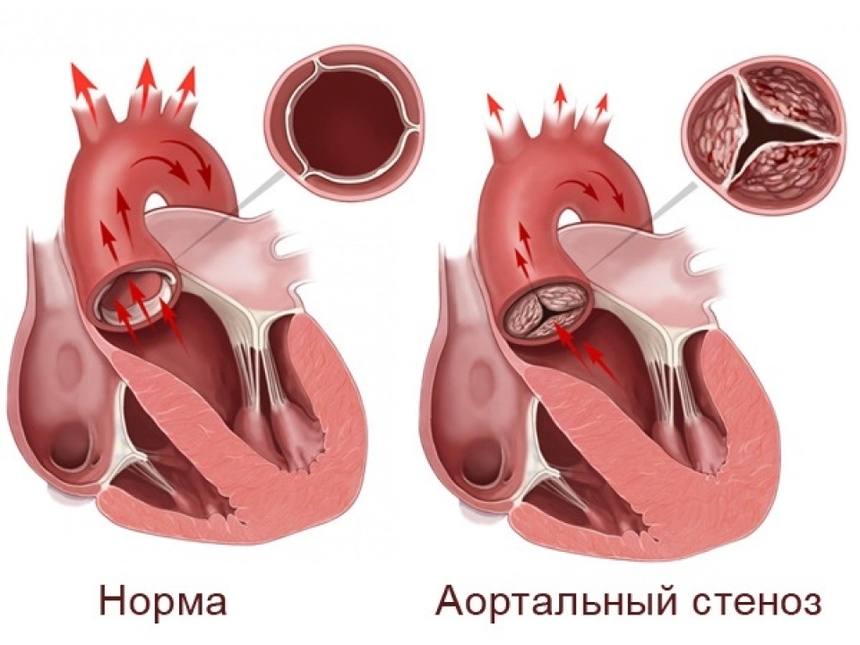

Пороки сердечно-сосудистой системы: виды и признаки